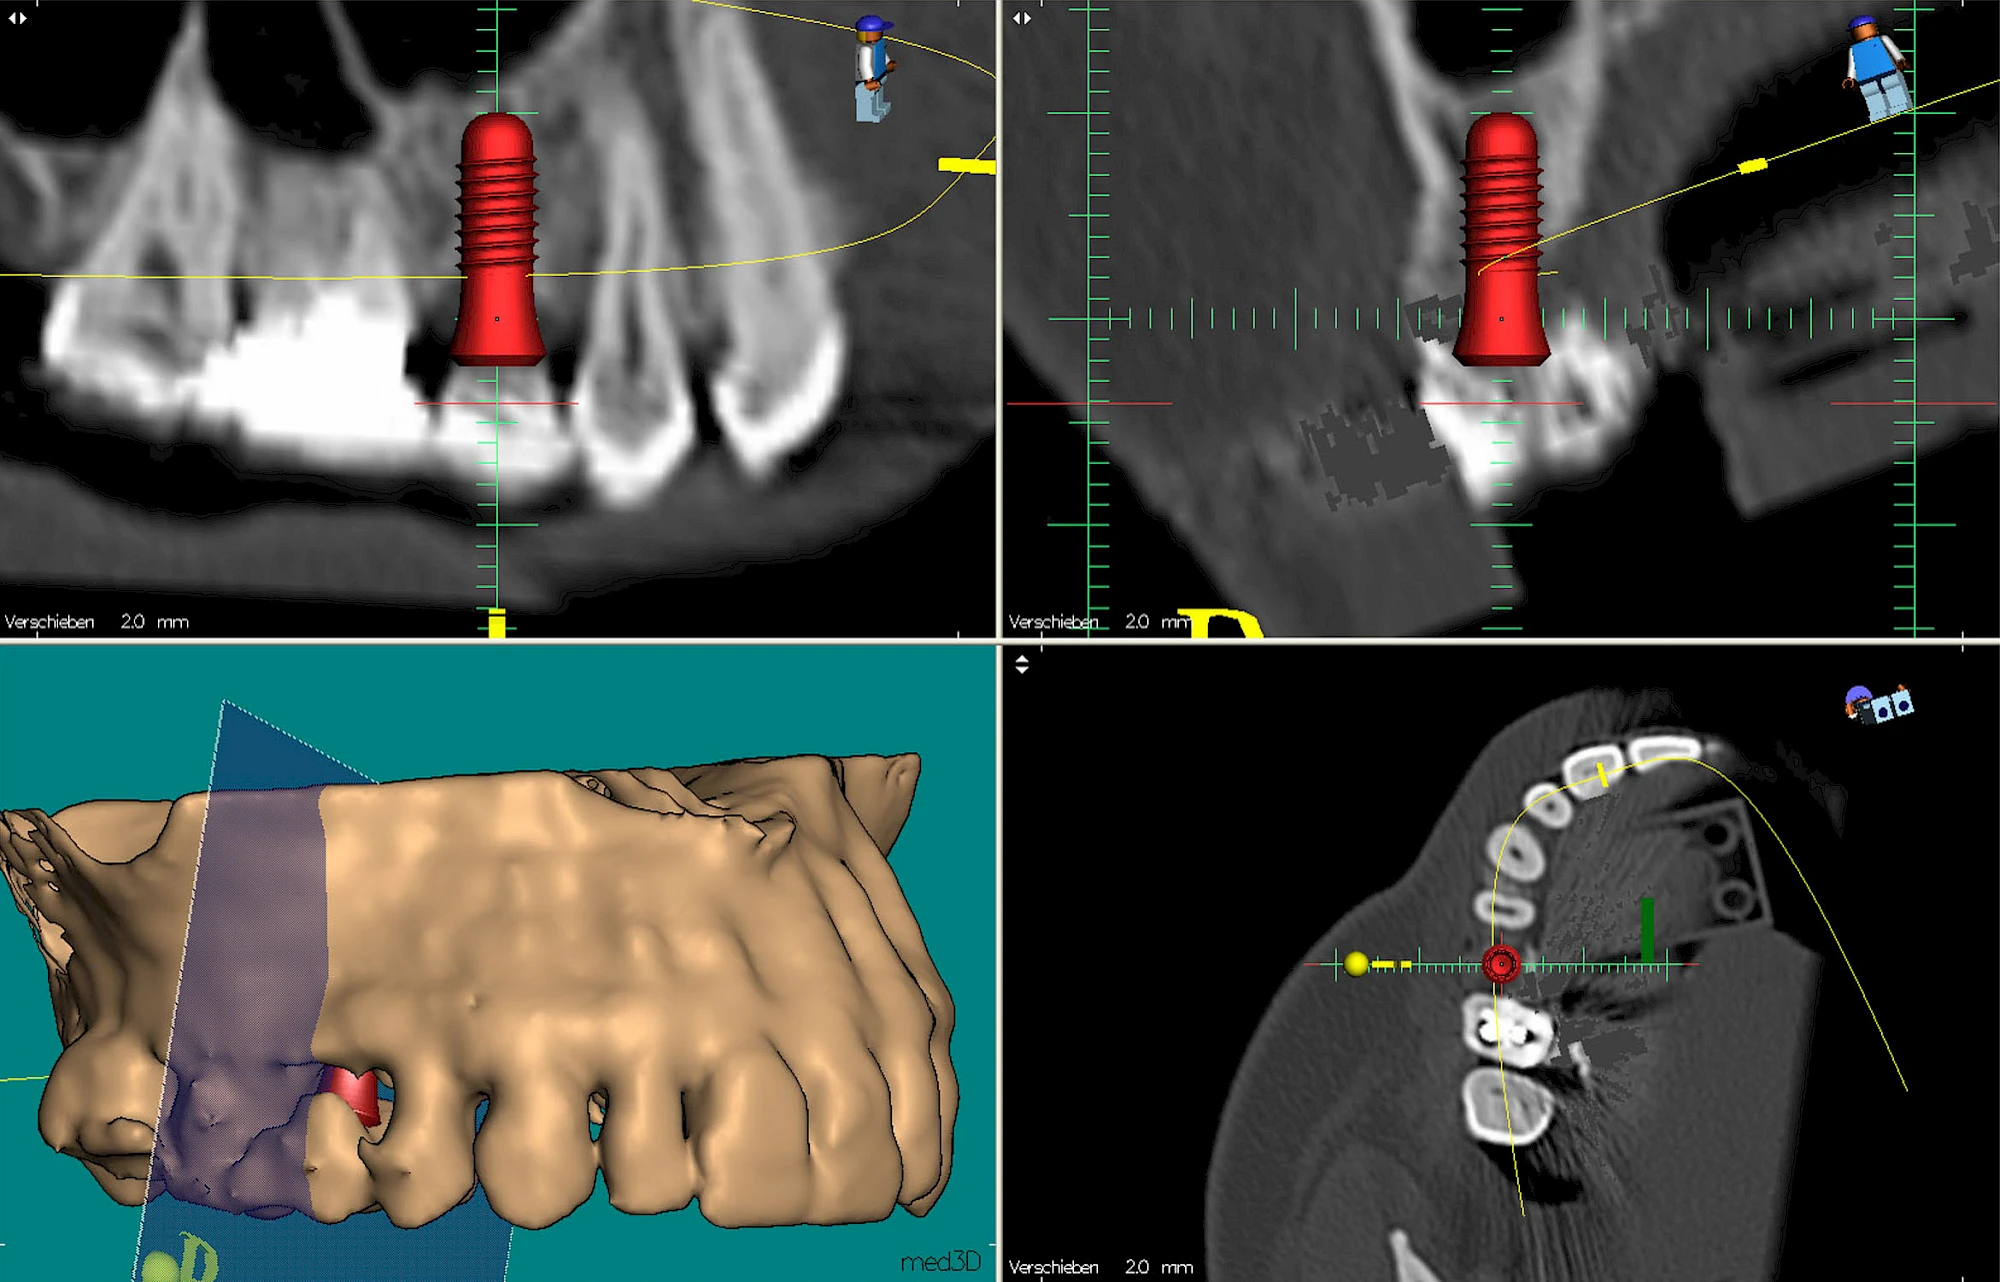

Implantatplanung

Damit Implantate an der richtigen Stelle im Kieferknochen platziert werden könen, gibt es heute vielfältige Möglichkeiten der Planung. In vielen Situationen kann die Erfahrung des Zahnarztes ausreichend sein.

Nicht selten ist jedoch auch eine technisch aufwändigere Vermessung im Vorfeld sinnvoll, z. B.:

- Wenn sich der Kieferknochen abgebaut hat

- Wenn der Nervverlauf im Unterkiefer beachtet werden muss

- Wenn die Ausdehung der Kieferhöhle im Oberkiefer beachtet werden muss

- Wenn wenige Restzähne keine gute Orientierung erlauben

In diesen Fällen kann die Planung mittels verschieden aufwendiger Röntgen-Techniken (Übersichtsaufnahme, DVT) ggf. unter Zuhilfenahme speziell angefertigter Planungsschablonen sinnvoll sein.